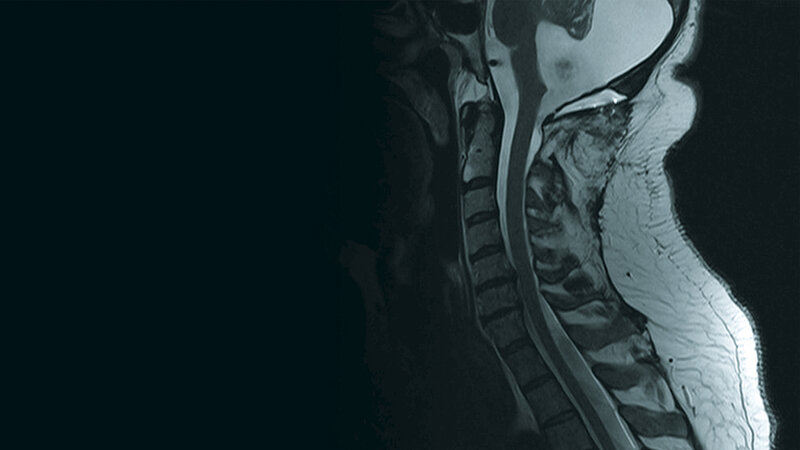

Schnittbilddiagnostik der Wirbelsäule (7.31)

Das Dandy-Walker-Syndrom ist eine der Malformationen der hinteren Schädelgrube. Es ist durch eine Hypoplasie des Vermis cerebelli, zystische Dilatation des 4. Ventrikels und Vergrößerung der hinteren Schädelgrube charakterisiert. Eine Assoziation der Dandy-Walker-Malformation und einer Syringomyelie ist sehr selten.